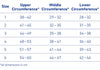

MEASUREMENT AND PRODUCT RANGE